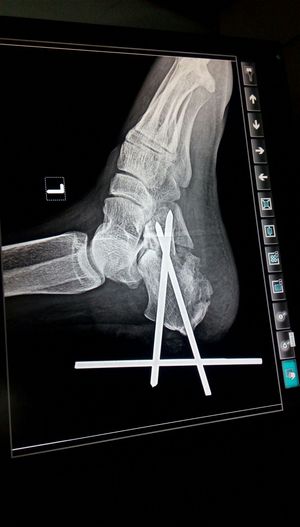

What type of surgery?

Surgery

Casestudy

Orthopedic

Osteosynthesis